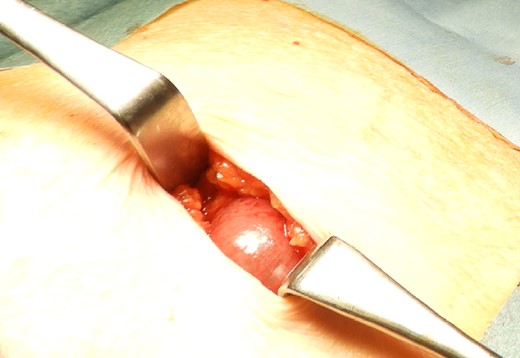

The drain was removed on postoperative day 2. On the night of the third postoperative day, the patient vomited. On the morning of the fourth postoperative day, mild abdominal pain and a ping-pong ball-sized bulge and induration were found near the surgical scar of the 5 mm port where the drain had been placed. CT confirmed an incarcerated small intestine and ileus in the 5 mm port scar where the drain had been placed (Fig. 2). Ileus removal was performed on the same day. First, the dilated wound for nephrectomy was opened, and the inside of the abdominal cavity was observed. A hanging small intestine was observed just below the 5 mm port (Fig. 3). Since it could not be conquered manually, a 2 cm vertical incision was made on the 5 mm port wound. The small intestine penetrated the anterior layer of the rectus abdominis muscle, so the fascia was carefully incised to avoid damaging the small intestine. The small intestine was returned to the abdominal cavity. The small intestine was slightly discolored (Fig. 4), but after discussion with the gastrointestinal surgeon, it was determined that it was not necrotic. No small intestine resection was performed. The wound was carefully closed using fascial sutures to prevent recurrence. The fascia was weak, likely because this patient was taking steroids. The ileus has not recurred since then. The pathological results indicated a maximum diameter of 30 mm, consistent with papillary renal cell carcinoma, classified as pT1a G3 > G2, with negative margins.

Small intestine incarcerated in the fascia of rectus abdominis.